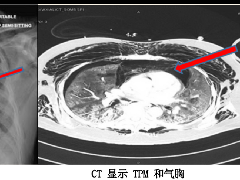

纵隔大细胞神经内分泌癌1例CT影像  张力性纵隔气肿影像表现及严重度分级